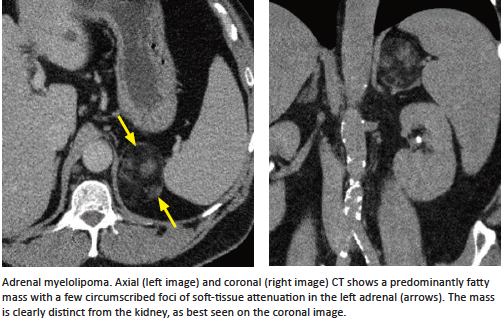

Adrenal Myelolipoma

What is it?

How to diagnose?

Don’t confuse this with what?